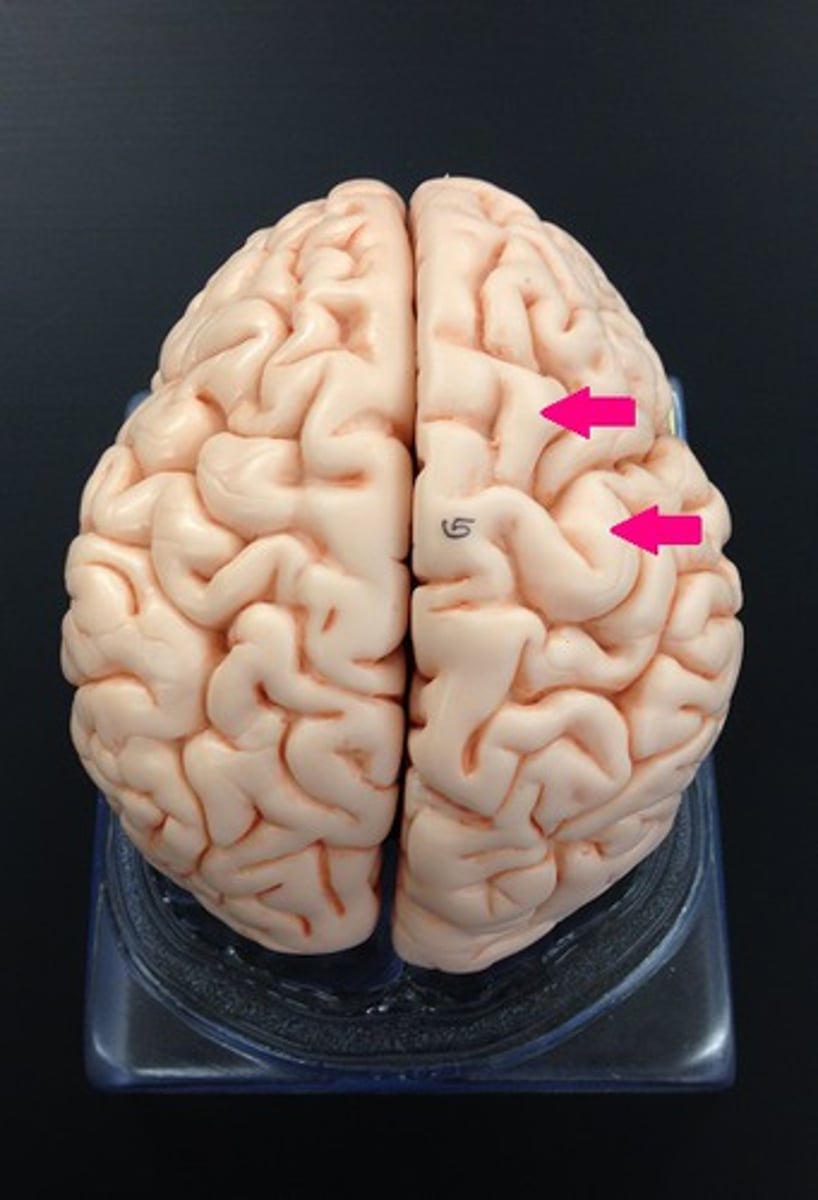

Superior Dorsal View of brain

Gyri

Sulci

Longitudinal Cerebral Fissure

Frontal Lobe

Parietal Lobe

Central Sulcus